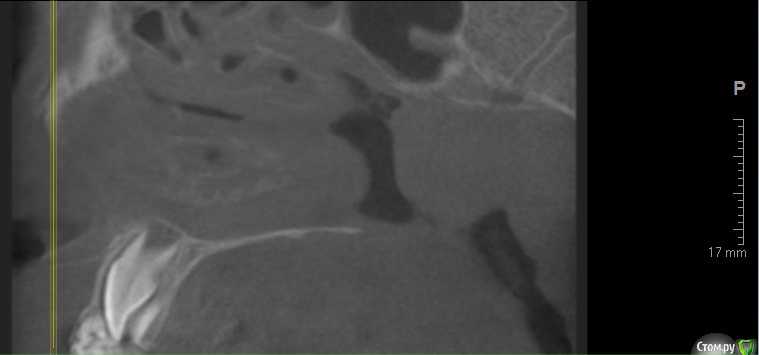

По данному случаю: пациент 6-7 лет, 21 не растёт, все динамят (ортодонты и терапевты), дошли до хирурга: на снимок прицельный, что то не то, на КТ охарактеризовал как одонтому. Операция под

анестезией Ультракаин дс, кортикальную пластинку трепанировал «расковырял» эскаватором, убрал конгломерат тведых тканей, саму оболочку, удалил 61. Биологический материал в пробирку с физ